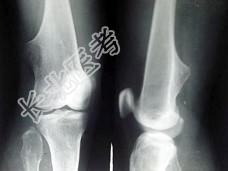

- 单项选择题女,15岁, 发现大腿远端肿块1周,无明显疼痛, 结合图像,最可能诊断是 ( )

A、骨质增生

B、软骨瘤

C、骨肉瘤

D、骨瘤

E、骨软骨瘤